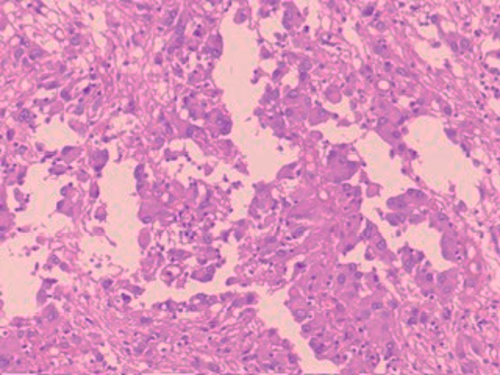

HISTOPATHOLOGY

What is the lesion seen in this section ?